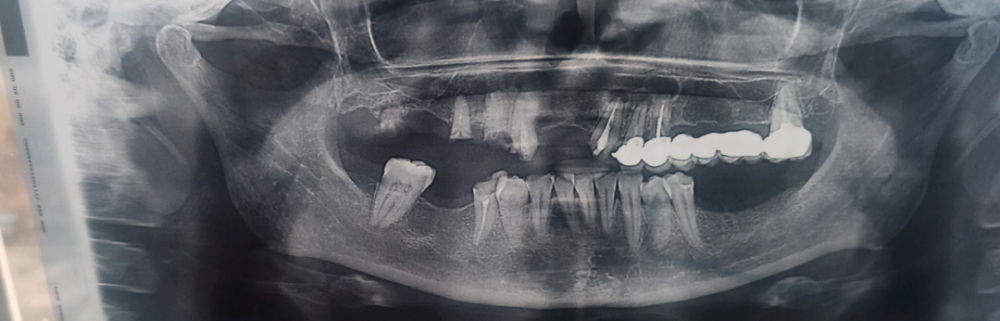

Likali Опубликовано 8 ноября, 2021 Поделиться Опубликовано 8 ноября, 2021 здравствуйте, можно ли закрепить коронку вверху слева на оставшихся корнях? или корни уже полностью разрушены и не удержат коронку на штифтах Ссылка на комментарий

Notherbrick Опубликовано 8 ноября, 2021 Поделиться Опубликовано 8 ноября, 2021 Если отталкиваться от предоставленной ортопантомогоаммы, а она малоинформативна, то очень маловероятно что сохранившиеся корни на верхней челюсти справа хоть сколько то состоятельны в качестве опорных для любых конструкций. И в цело состояние зубочелюстной системы требует гораздо более комплексного подхода. Ссылка на комментарий